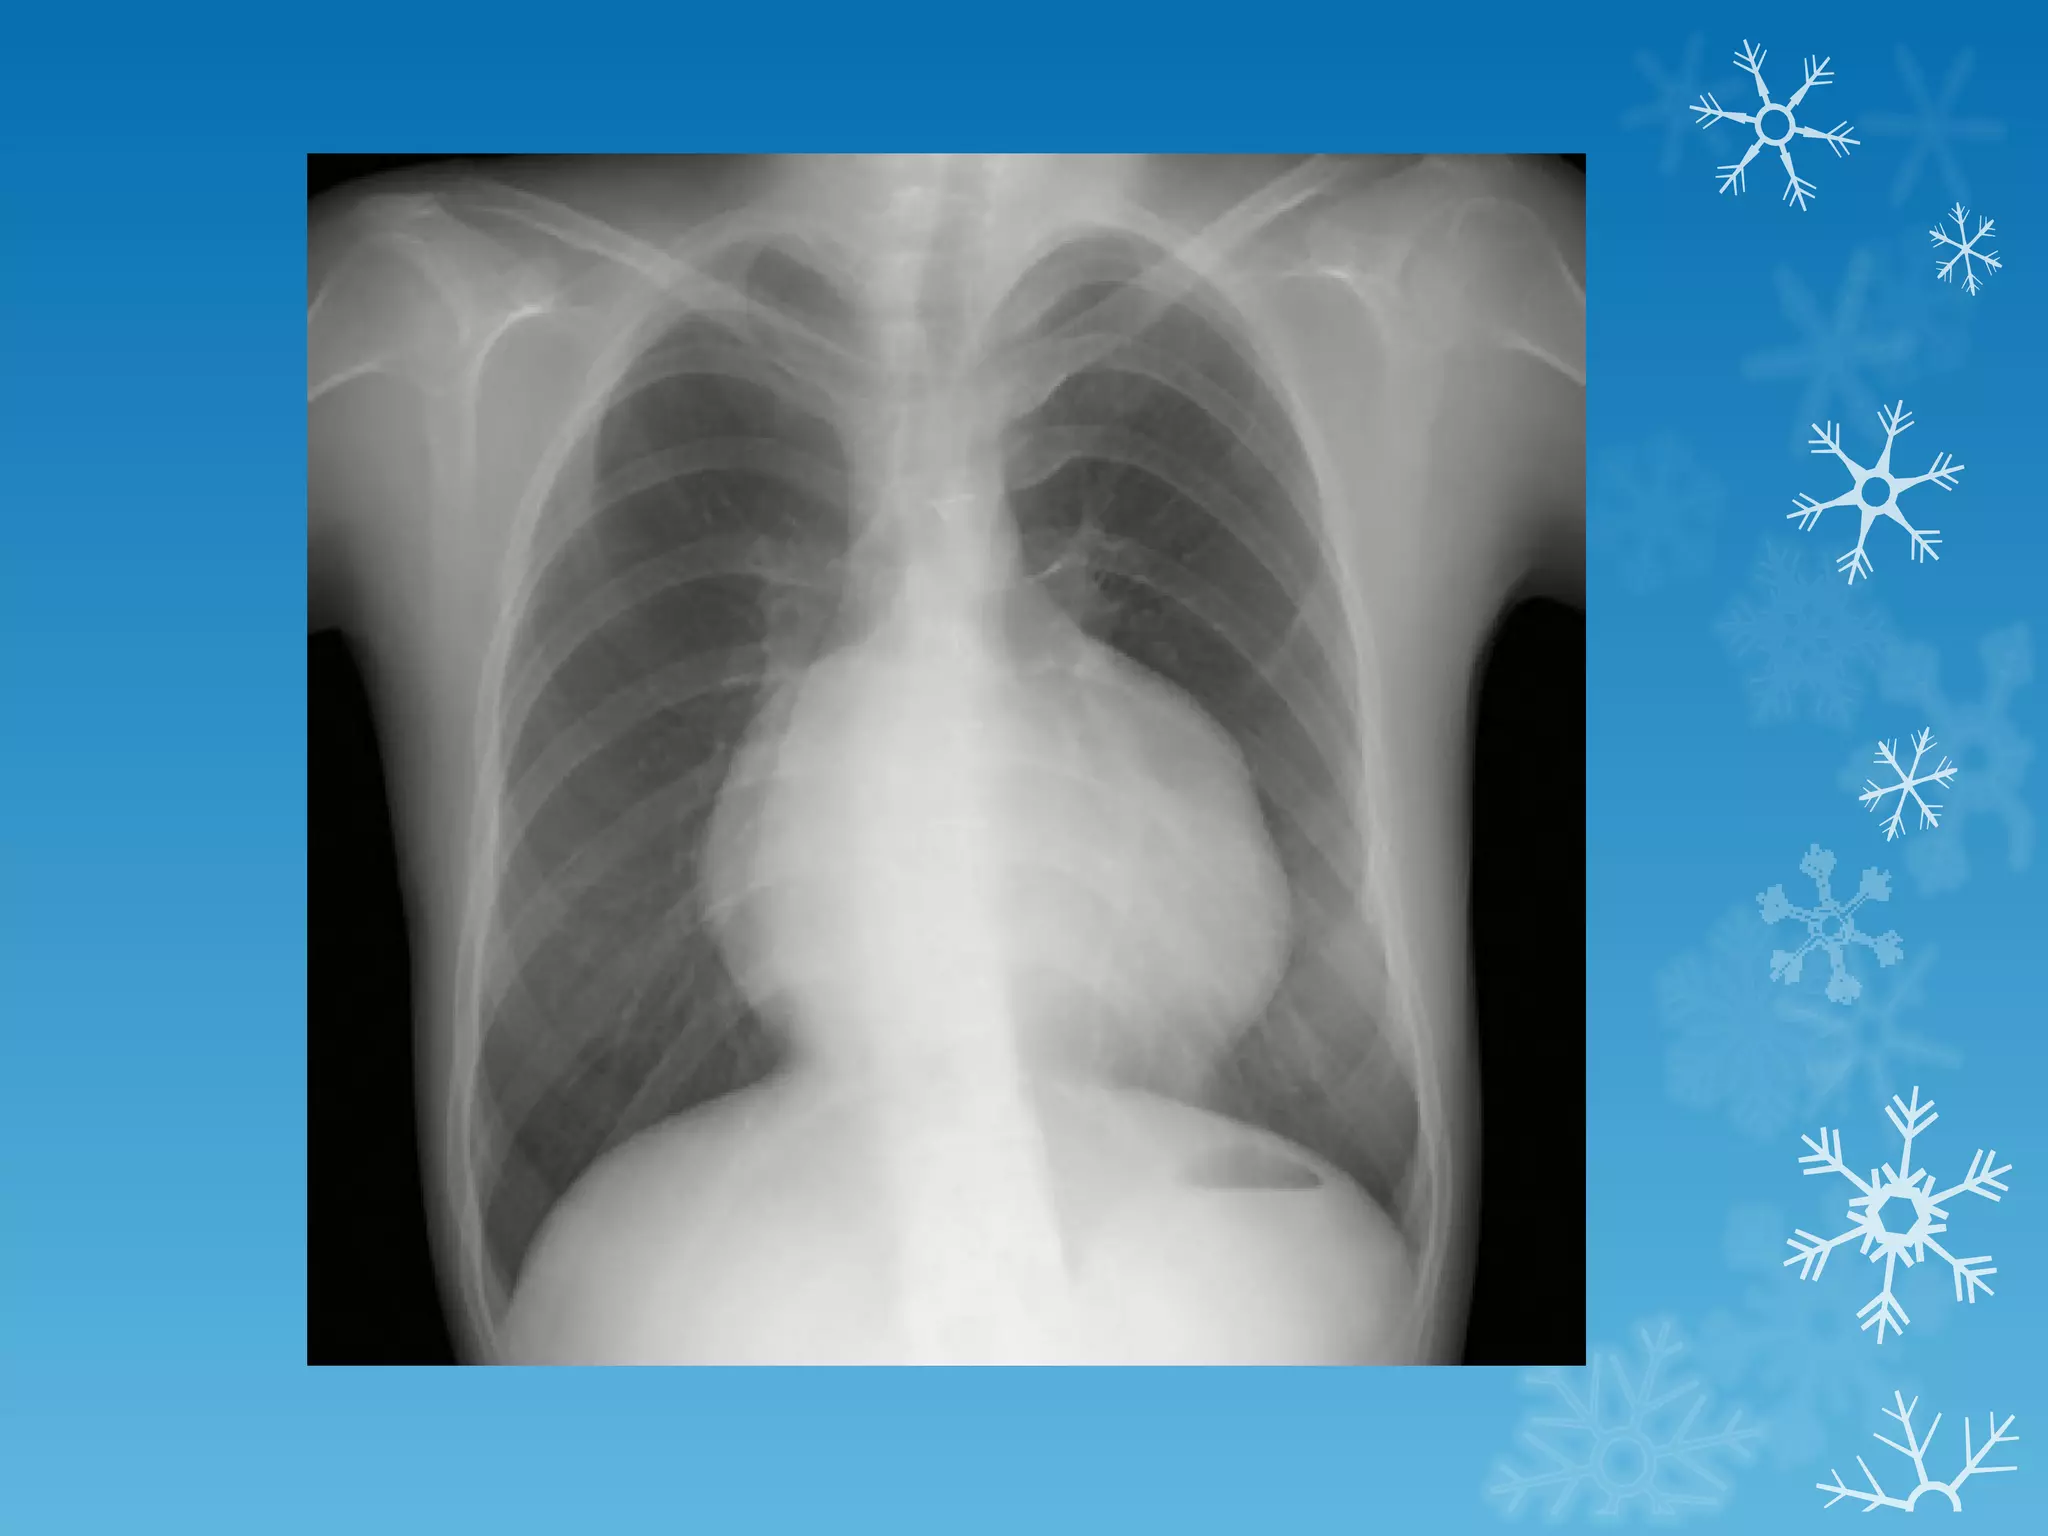

This document discusses chest x-ray interpretation and provides guidance on evaluating x-rays. It explains that tissue density determines how an x-ray beam penetrates, with denser tissues appearing whiter and less dense tissues appearing blacker. It also outlines different chest x-ray views and factors to consider like patient orientation, age, gender, and rotation. Abnormalities are described as appearing too white, too black, too large, or in the wrong place. The document stresses a systematic approach of identifying, localizing, describing lesions, and providing differential diagnoses.